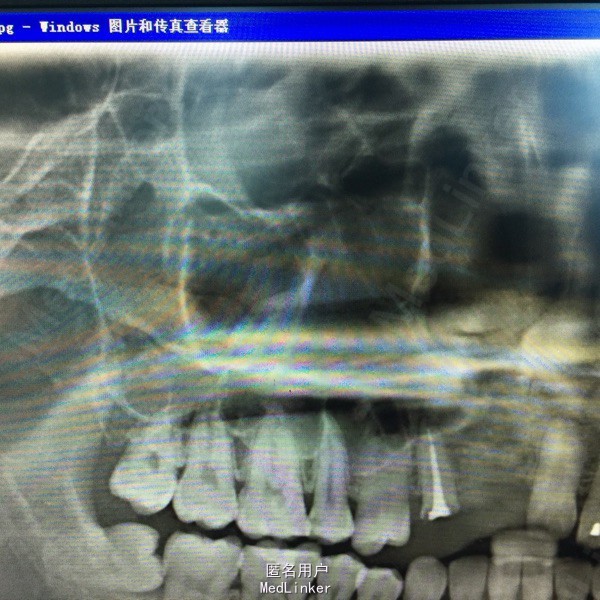

上前牙烤瓷冠修复,13牙冠缺损,叩(+),行桩冠修复。曲面断层片示:13、14根尖可见4x2cm阴影,边缘可见白色阻射线。

诊断:13、14根尖囊肿 处理:1、拆除桩冠。 2、13行牙髓治疗。 3、囊肿行开窗引流术。

患者每天以生理盐水冲洗,2一4次/天,半年复查X片。 该患者1年半后,可见囊腔缩小,新骨长入。无需行囊肿挖除术。